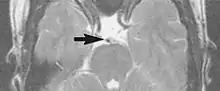

A motion artifact is one of the most common artifacts in MR imaging.[2] Motion can cause either ghost images or diffuse image noise in the phase-encoding direction. The reason for mainly affecting data sampling in the phase-encoding direction is the significant difference in the time of acquisition in the frequency- and phase-encoding directions.[1]

Frequency-encoding sampling in all the rows of the matrix (128, 256 or 512) takes place during a single echo (milliseconds). Phase-encoded sampling takes several seconds, or even minutes, owing to the collection of all the k-space lines to enable Fourier analysis. Major physiological movements are of millisecond to seconds duration and thus too slow to affect frequency-encoded sampling, but they have a pronounced effect in the phase-encoding direction. Periodic movements such as cardiac movement and blood vessel or CSF pulsation cause ghost images, while non-periodic movement causes diffuse image noise (Fig. 1). Ghost image intensity increases with amplitude of movement and the signal intensity from the moving tissue. Several methods can be used to reduce motion artifacts, including patient immobilisation, cardiac and respiratory gating, signal suppression of the tissue causing the artifact, choosing the shorter dimension of the matrix as the phase-encoding direction, view-ordering or phase-reordering methods and swapping phase and frequency-encoding directions to move the artifact out of the field of interest.[1]